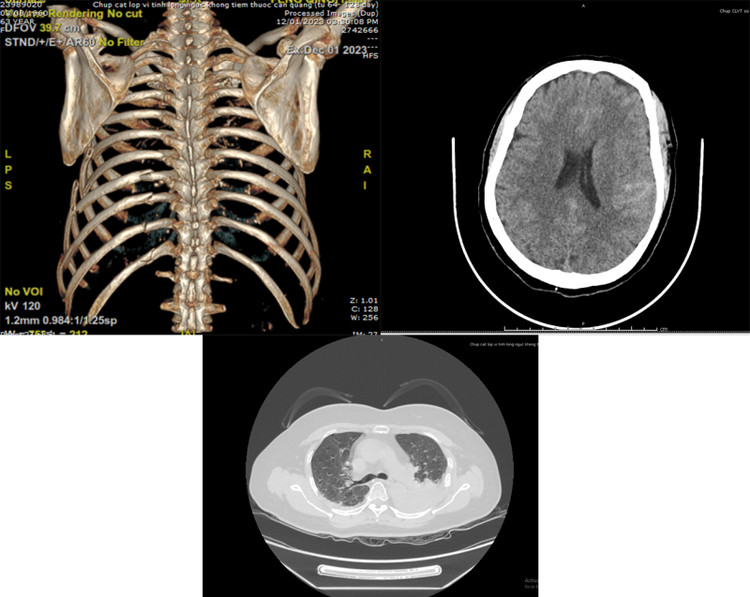

Qua thăm khám lâm sàng, thực hiện các xét nghiệm, chẩn đoán hình ảnh chuyên sâu như siêu âm, xquang, chụp CT Scanner..., các bác sĩ đã hội chẩn và thống nhất chẩn đoán đa chấn thương gồm: chấn thương sọ não (xuất hiện dưới nhện bán cầu não trái), chấn thương lồng ngực (gãy phức tạp nhiều xương sườn, dập phổi, tràn dịch màng phổi trái), vỡ thận, gãy cung tiếp gò má trái.

| Hình ảnh chấn thương lồng ngực, sọ não, thận của bệnh nhân trên phim chụp CTscanner |